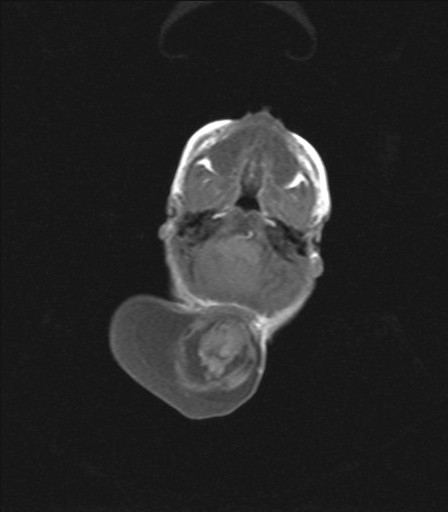

Encephaloceles

Encephaloceles are often grotesque-looking congenital swellings arising from the head or face, that may make childbirth difficult. Child often appears to have a swelling as large as the head. Most of these swellings can be surgically removed successfully.